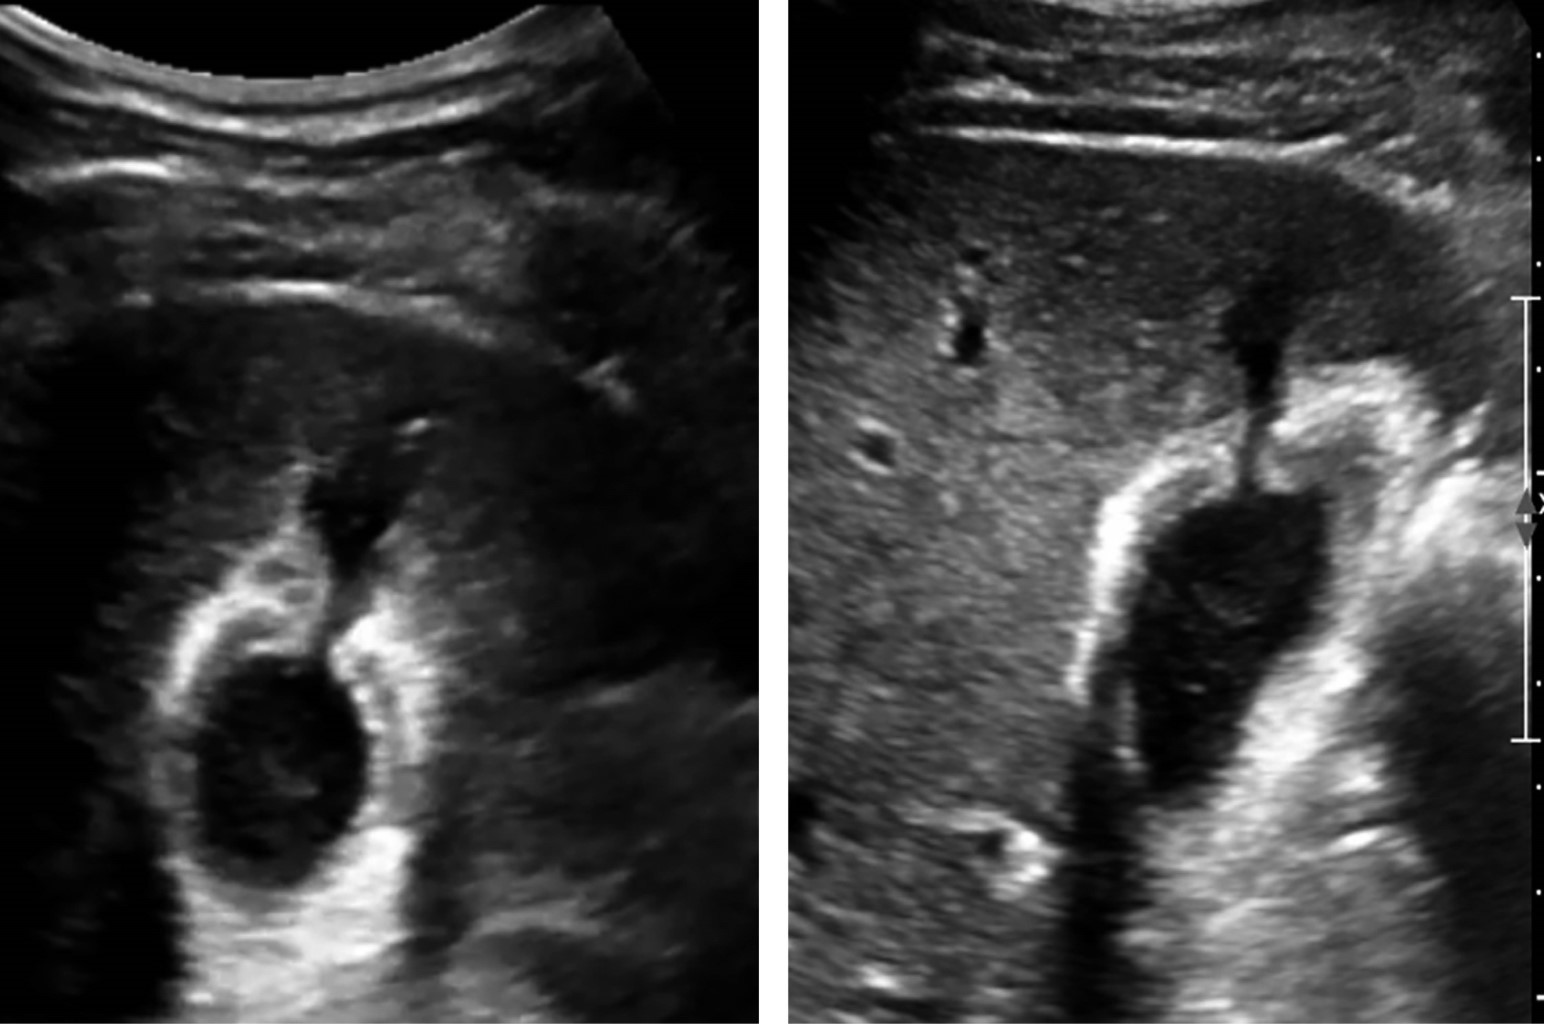

Se decide continuar vigilancia y realizar USG de control a las 27 horas de evolución, en el cual se reportó laceración hepática grado I de la AAST (American Association for the Surgery of Trauma) de 60 mm en su eje longitudinal, y vesícula biliar como se describe en la Figura 2.

Se realiza USG de control que reportó vesícula biliar con paredes engrosadas hasta 8 mm, edema perivesicular, a nivel del fondo pérdida de la continuidad donde discurre líquido de aspecto hipoecoico similar a contenido vesicular de 3.2 cm3 (hemobilia), sin evidencia de líquido libre en cavidad abdominopélvica (Figura 5).

A un mes de su egreso, se presenta en consulta sin presentar cuadro de dolor abdominal o cambios que afecten su calidad de vida, realizando sus actividades de la vida diaria. Se cita nuevamente a siete meses de su alta con USG de hígado y vías biliares de control en el que no se observan datos de proceso inflamatorio agudo en vesícula biliar (Figura 6), asimismo clínicamente se refiere asintomático, se decide alta del servicio.

La ecografía abdominal puede ser efectiva mediante la identificación de contenido hiperecogénico en la vesícula, líquido libre perivesicular y solución de continuidad de la pared vesicular, pared vesicular hipoecoica, edematosa engrosada, colapso a pesar de ayuno prolongado se correlaciona con colecistitis aguda.4